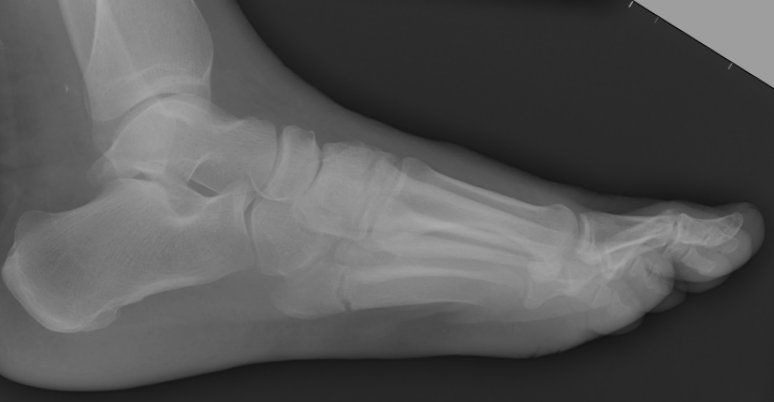

Return to Jones Fracture